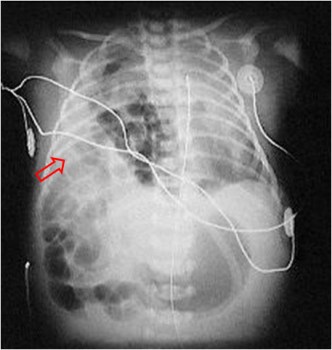

SIGNO DEL HÍGADO AUSENTE

La identificación de aire intestinal en el hemitórax derecho (en la placa de tórax de un neonato) –flecha- permite realizar el diagnóstico de hernia diafragmática congénita. En aquellos casos en los que únicamente se produce la herniación del hígado, el diagnóstico suele ser erróneo. La combinación de la opacificación del hemitórax junto a la presencia de aire intestinal en el cuadrante superior derecho (Signo del hígado ausente), debe sugerir el diagnóstico de hernia hepática intratorácica.